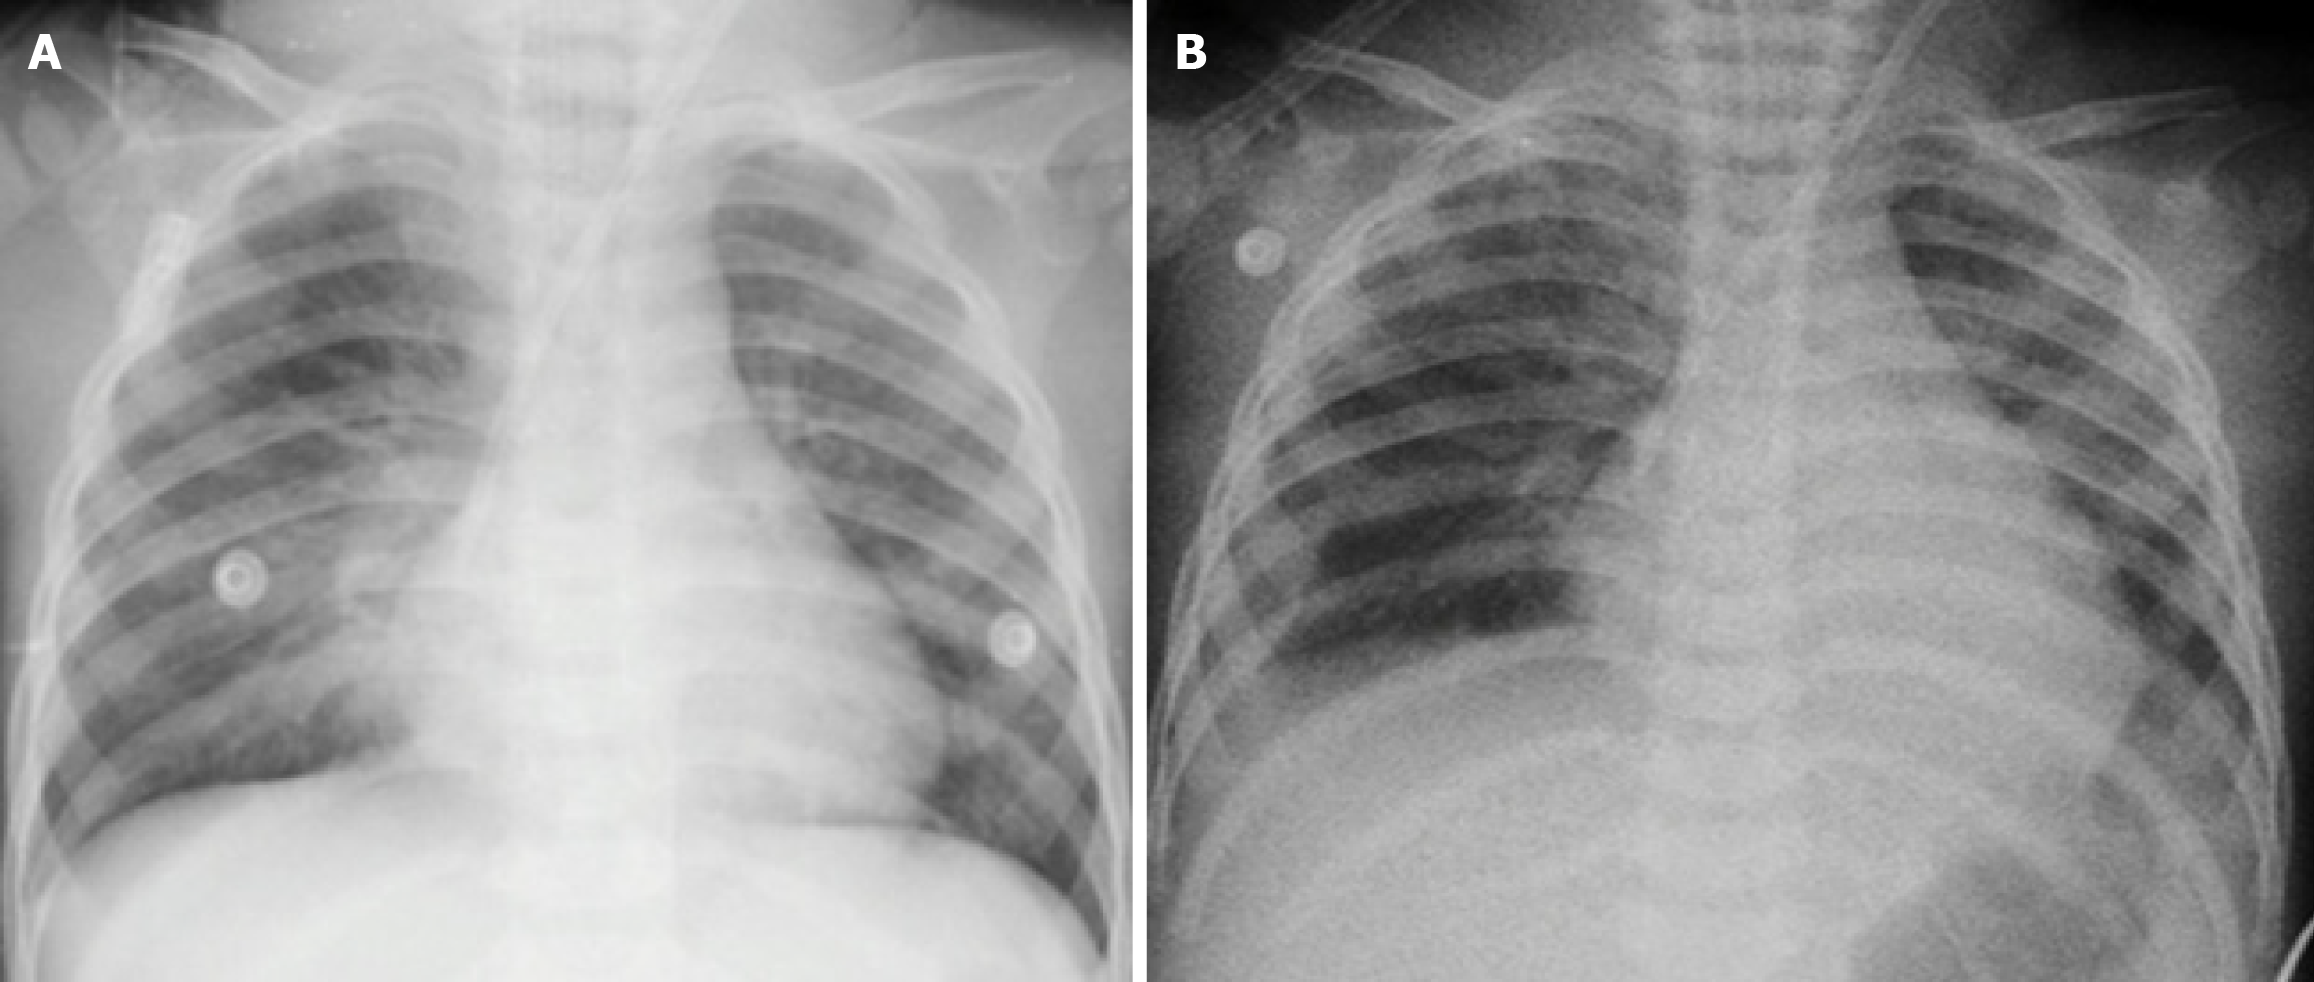

Figure 3 Chest X-ray findings.

A: Acute pulmonary edema at admission; B: Significant improvement after 5 days of mechanical ventilation, combined continuous renal replacement therapy and plasma exchange.